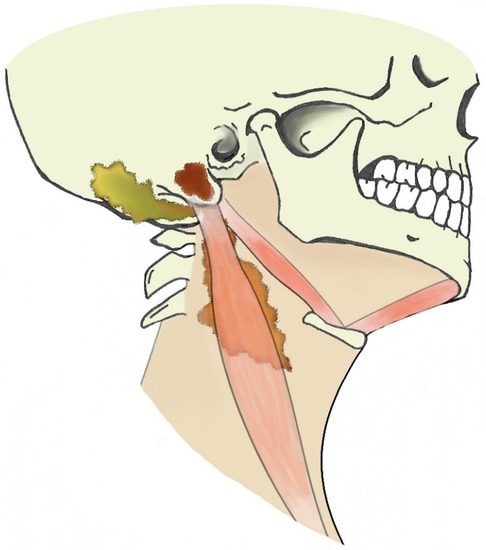

The role of MRI in the diagnosis of Bezold’s abscess is generally limited, being a “problem solving modality" used when intracranial complications or osseous disease are expected. In literature, MRI findings are reported for only 21/97 patients. Indeed, the first MRI report dates to 2001. The low rate of MRI reports likely depends on two concomitant factors: MRI was not available at diagnosis and CT was considered sufficient for proper surgical planning and patient management. However, MRI might be better in specific clinical circumstances (for example, when intracranial complications are present, a cholesteatoma is suspected, the purulent content of intracranial or neck collections should be proven) as diffusion-weighted imaging (DWI) best differentiates non-infectious fluid collections from bacterial abscesses.

Bezold’s abscess entails a moderate risk of intracranial vascular (23/97) or further infectious (9/97) complications. MRI protocols should therefore include DWI and vascular imaging. DWI best recognizes suppurative collections (abscess, empyema, or even intraventricular debris) showing hyperintense signal on DWI with usually decreased apparent diffusion coefficient values (i.e., restriction of water molecule diffusion). DWI also detects cytotoxic oedema and intravascular thrombi helping in recognizing recent ischemic strokes or sinus venous thrombosis. Artery and venous intracranial MR-angiography can detect vessel occlusion consistent with thrombosis, thus confirming CT-angiography findings and allowing a less invasive follow-up. These sole sequences cover most intracranial complications of mastoiditis associated with Bezold’s abscess and are therefore of utmost importance for subsequent patient management.

In the literature, cholesteatoma ipsilateral to Bezold’s abscess was reported in around 40% of patients. Cholesteatoma likely favors repeated mastoid bacterial superinfections and facilitates, by bone erosion, the spread of suppurative process into the neck (see Section 4.2). In several patients, cholesteatoma was diagnosed at surgery (11/97) and in a few cases it was partially an unexpected finding. However, MRI might easily recognize cholesteatoma preoperatively as these cysts appear as strikingly hyperintense DWI ovoid masses [42]. Differently from purulent collections, apparent diffusion coefficient (ADC) values might be slightly increased in cholesteatomas, suggesting a T2 shine-through effect more than a true water diffusion restriction [55]. From a technical point of view, whereas investigating the mastoid and the upper neck, non-echo-planar (non-EPI) DWI sequences should be preferred to minimize mastoid air/bone susceptibility artifacts that could mask the cholesteatoma [56]. DWI represents a very powerful tool also in postoperative and follow-up examinations, allowing for the detection of small cholesteatomatous residuals or recurrences (Figure 6), especially those with a diameter larger than 2–4 mm [57].

Figure 6. Thirty-seven-year-old man with chronic otitis media and history of ear surgery. MRI T1w (a) and contrast-enhanced T1w (b) sequences showing hypo-isointense material in the left mastoid (black arrows) spreading in the neck, in the posterior cervical space (white arrowheads). Note the mastoid mucosal enhancement, suggestive for mastoiditis, and the peripheral enhancement of the neck component (b). The material in the mastoid is hyperintense in diffusion-weighted imaging (c) and shows inhomogeneous apparent diffusion coefficient values (d), consistent with purulent collection and cholesteatoma. Bezold’s abscess and left mastoid cholesteatoma were confirmed at surgery.